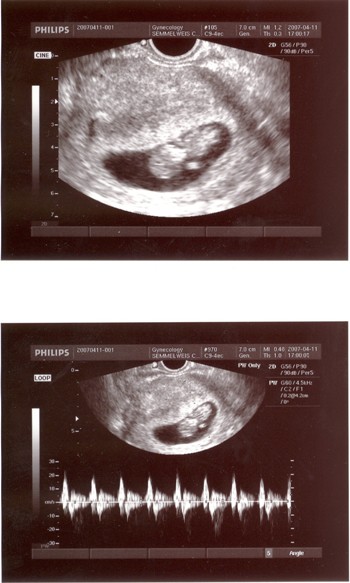

A dokim szerint UH-val szépen látható az, amit ez szűr, de talán mégis megnyugodnék, és elmennék. A 4D-s UH-t, a nyaki redő szűrést is azon kereten belül csinálták? Attól függetlenül elmentél a dokidhoz is? Mert én 2 hét múlva megyek a saját dokimhoz nyaki redő szűrésre, és ha itt is csinálnak... nem tudom, picit azért tartok a sok UH-tól!